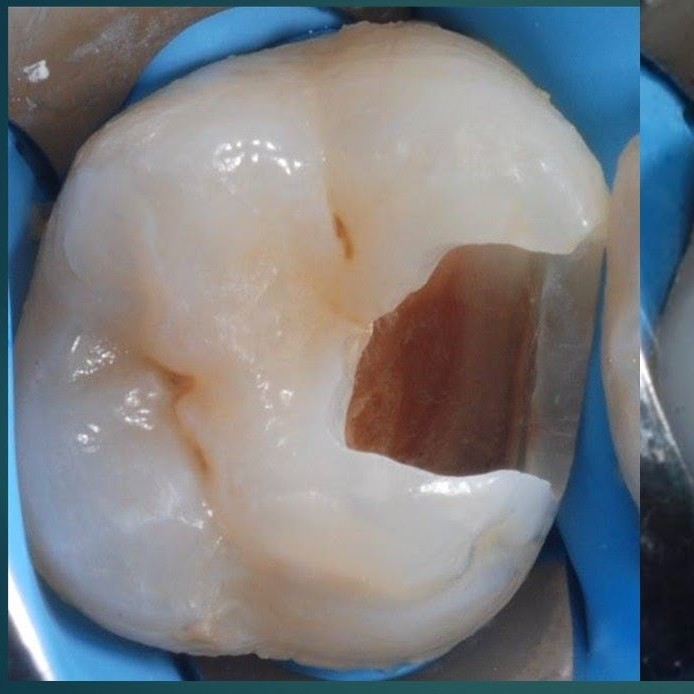

Penambalan Gigi Geraham Besar atau Kecil

Karies Gigi/Lobang Gigi Berlokasi Masi Pada Bagian Atas Mahkota gigi. Seperti Contoh pada Gambar